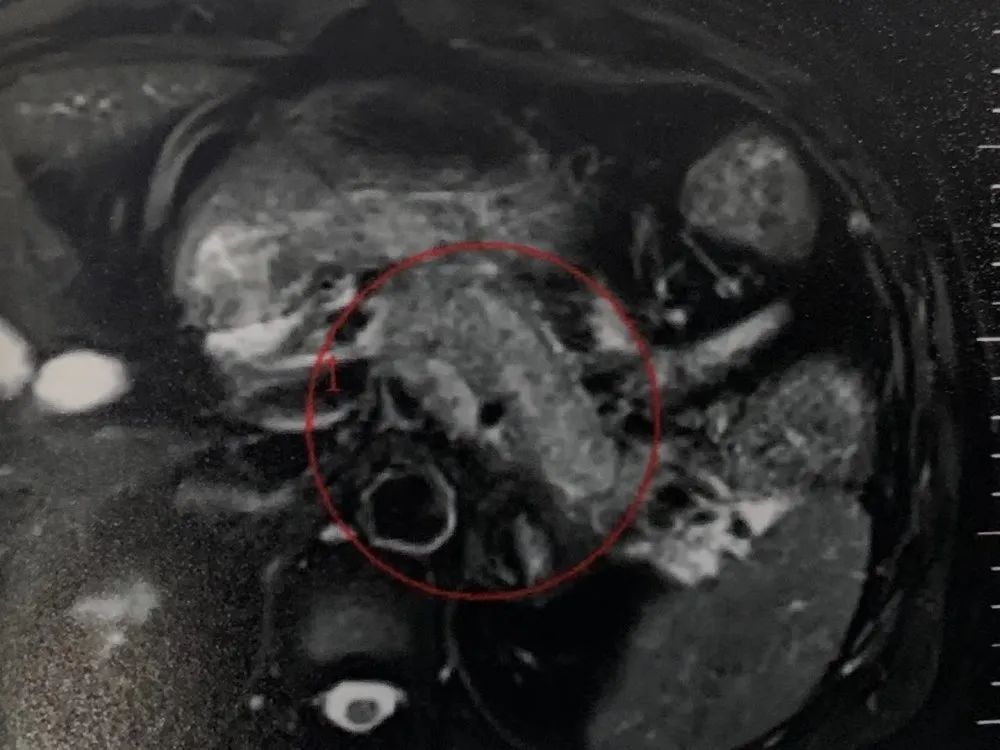

5月7日PET-CT檢查發(fā)現(xiàn):胰腺體尾部增粗伴周圍滲出性改變,F(xiàn)DG高代謝,惡性腫瘤可能性大;左側(cè)腎上腺術(shù)后,左側(cè)腎上腺區(qū)不均質(zhì)密度占位。為更進一步了解病情,隨后許先生在5月13日做了腹部、盆腔增強CT:胰腺體尾部惡性腫瘤伴左腎上腺受累,脾靜脈、腸系膜上靜脈及門脈主干受累可能性大;并在上海某醫(yī)院接受胰腺腫瘤穿刺活檢,病理顯示:胰腺低分化腺癌。